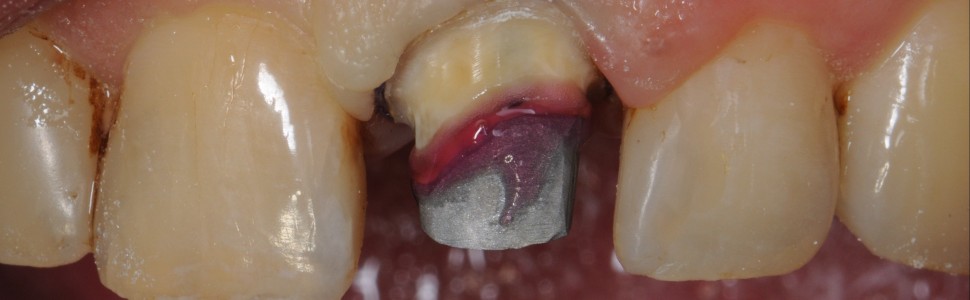

Korony tymczasowe są elementem przejściowym, użytkowanym do czasu osadzenia ostatecznego uzupełnienia protetycznego. Zdarzają się jednak sytuacje, gdy czujemy się w obowiązku sprostać oczekiwaniom pacjenta i wykonać uzupełnienie, które przetrwa znacznie dłużej. W artykule omówiono przypadek wykonania natychmiastowego uzupełnienia tymczasowego, zindywidualizowanego materiałem kompozytowym w celu zapewnienia lepszej estetyki w odcinku przednim.